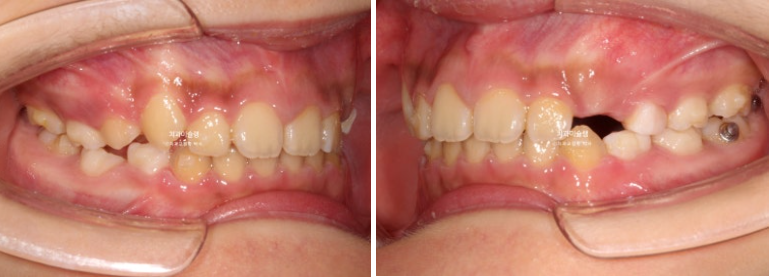

23.11

2년 전 교정치료를 위해 온 만 10세 어린이 입니다.

앞니가 하나 들려있고 깊게 물리는 과개교합이 있습니다.

중심선 불일치도 보입니다.

윗니 돌출이 측면에서 잘 보이네요.

영구치날 공간은 비교적 양호한 편입니다.

파란화살표 자리에 있어야할 작은어금니가 선천적 결손 상태입니다.